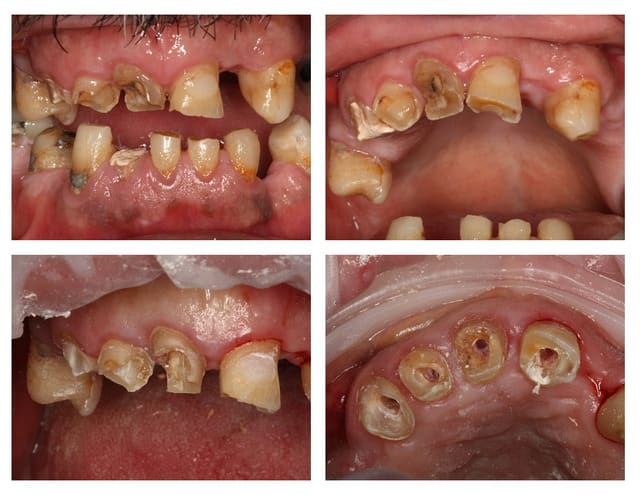

Tiens dans la serie question stupide

Patient adulte male méditeranéen 50 ans

Ancien fumeur et buveur

Parodontite chronique generalisée severe sur 80% modérée sur 20% . Indice de plaque 110%.

Supraclusion avec morsure palatine

Bruxisme diurne unilatérale ( coté gauche pour ceux qui n'avait pas vu ) suite a la perte du calage postérieur et de la DV il y a plusieurs années.

Il a comme exigence 1 : Ne pas poser d'implants ( tabac/argent) 2:Ne pas toucher aux dents saines (31 41 42 43 44 ).

Alors Ceramik IC or not :) ?